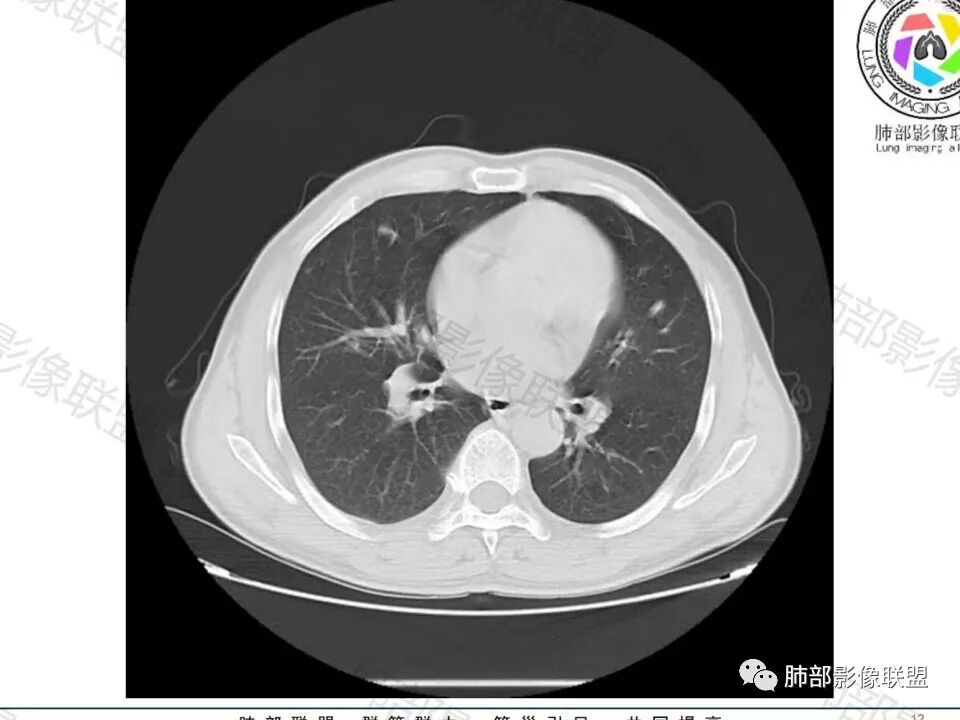

男,60体检发现左肺下叶结节,左肺下叶类圆形结节影,边界清晰,边缘见浅分叶及细短毛刺,病灶内见增粗血管影穿行,相应层面胸膜增厚,双肺另见微小结节影,增强扫描病灶轻度强化,考虑隐球菌,除外腺癌。

老年男性,左肺下叶背段胸膜下孤立结节,整体圆顿,周围有晕,晕中毛刺,似乎支持隐球,但边缘有一囊腔,恶性不能除外!等答案!

左肺下叶胸膜下类圆形结节,无分叶,无胸膜牵拉,周围有晕,血管支气管进入,考虑隐球菌

左下肺、右中肺均有结节,左下肺病灶比较鼓,边缘有晕,血管弯,持续性强化,考虑腺癌可能,鉴别两处病灶如果一元论,肉芽肿炎 (隐球)

老年男性,CT左肺下叶胸膜下类圆形结节,边缘光滑,无分叶,可见毛刺,相邻胸膜多条牵拉,局部胸膜增厚,(多见炎性病变),病灶周围可见模糊晕征,血管支气管进入,考虑隐球菌,现实中万万不能排除肺癌。

中老年男性患者,无症状体检发现,胸部CT:左下肺内前基底段近胸膜下类圆形结节,边缘清晰,周围晕征,周围毛刺细软,有胸膜牵拉及血管进入,增强扫描明显不均匀强化,考虑炎性肉芽肿,隐球菌可能,鉴别腺癌

图做的真漂亮!老年男性,双肺多发结节,最大者位于左肺下叶胸膜下,周围有晕,晕中毛刺,边缘有一囊腔,胸膜牵拉,持续强化,考虑隐球,鉴别腺癌。

左肺下叶胸膜下类圆形结节,边缘光滑,周围有晕,晕中有毛刺,周围可见小卫星灶,相邻胸膜增厚,血管进入,右肺中叶可见小结节影,考虑炎性肉芽肿,隐球菌。鉴别腺癌。

晨读:左肺下叶胸膜下实性小结节,边缘可见模糊晕及毛刺,轻度收缩,与支气管关系不清,近端与血管束相连,内见小空泡,平扫密度均匀,均匀强化。远近可见多个小结节。考虑炎性肉芽肿,隐球菌病,鉴别结核、腺癌。

老年男性,左肺下叶背段胸膜下结节,边缘毛刺,血管进入,斜裂有牵拉,局部胸膜糊墙,周围有晕,但有一囊腔,首先考虑腺癌,但是右肺中叶及左肺下叶还有其他结节,鉴别隐球菌

多发类似结节

1、炎性结节,多发,类似,晕,隐球菌?

2、恶性:多发:转移瘤?肺癌并多发转移瘤?